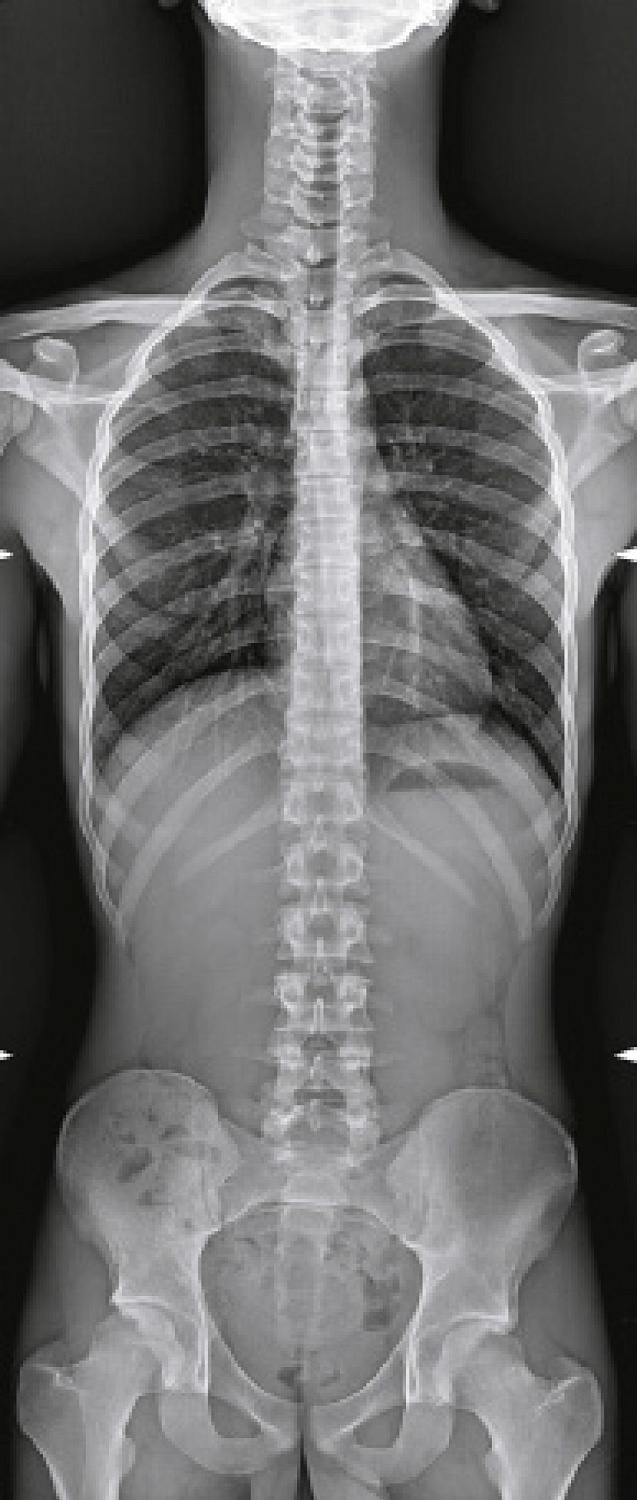

Аппарат позволяет проводить исследования как детей, так и взрослых, обладает максимальными возможностями в части охвата в продольном и поперечном направлениях, проведении исследований без перемещения пациента, выбора фокусного расстояния, наклона и поворота излучателя. Продуманная конструкция комплекса дает возможность свободно подходить к столу с любой стороны, а габариты и большой диапазон изменения высоты деки облегчает процесс укладки пациентов, что очень удобно для позиционирования пожилых и травмированных пациентов, людей с ограниченными возможностями, детей.